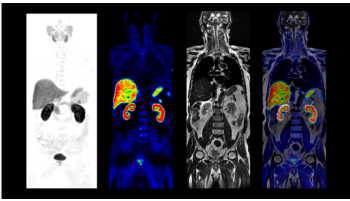

IV.4.7.3. PET–CT